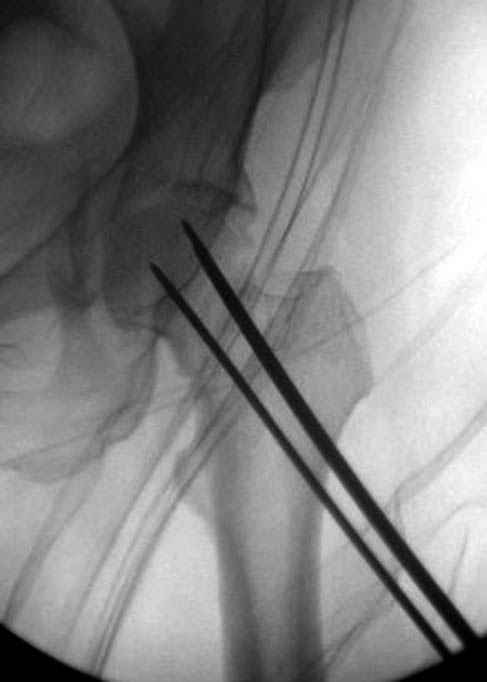

В данный момент скелетное вытяжение получается через перелом шейки, а

фиксированный перелом шейки будет участвовать в процессе вытяжения через

канюлированные  шурупы.

Имя     : 5 fem neck CRM.jpg

Тип     : image/jpeg

Размер  : 18998 байтов

Описание: отсутствует

Url     : http://weborto.net:8080/pipermail/ortho/attachments/20080116/651190cc/attachment-0010.jpg

Имя     : 6 fem neck CRM.jpg

Размер  : 24442 байтов

Url     : http://weborto.net:8080/pipermail/ortho/attachments/20080116/651190cc/attachment-0011.jpg